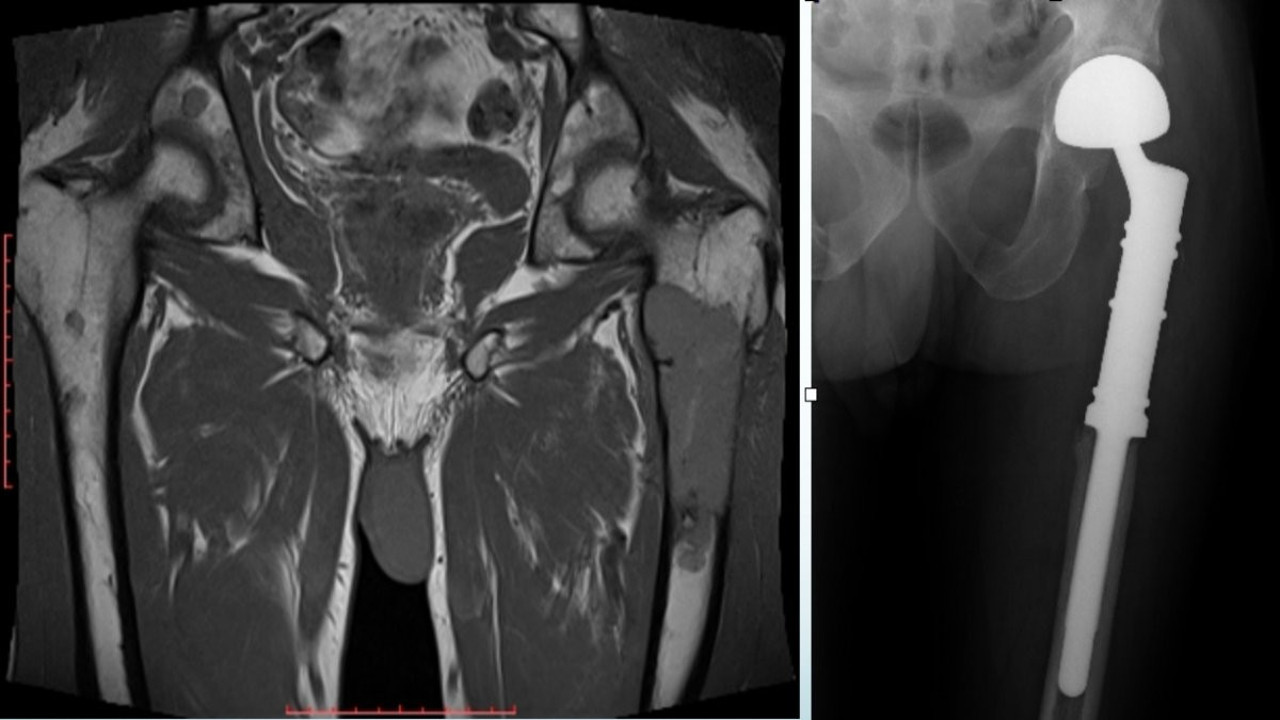

4. Kemik Sağlığını Destekleyen Tedaviler: Osteoporozu önlemek ve kemik kırıklarını azaltmak için kullanılan bifosfonatlar ve diğer destek tedaviler, hastaların yaşam kalitesini artırmakta.